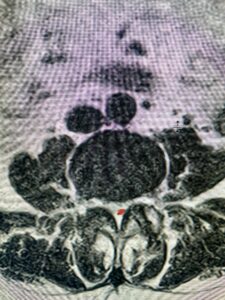

Fig 1b: Axial lumbar T2-weighted MRI demonstrating severe lumbar stenosis (red dot)